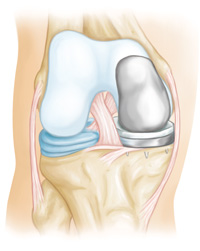

Parts of a posterior-stabilized implant (arrow) replace the PCL.

A cruciate-retaining component is designed with grooves to accommodate a patient's PCL.

One of the most commonly used type of implant in total knee replacement is a posterior-stabilized component. In this design, the cruciate ligaments are removed and parts of the implant substitute for the posterior cruciate ligament (PCL).

The tibial component has a raised surface with an internal post that fits into a special bar (called a cam) in the femoral component. These components work together to do what the PCL does: prevent the thighbone from sliding forward too far on the shinbone when you bend your knee.

As the name implies, the posterior cruciate ligament is kept with this implant design (the anterior cruciate ligament is removed). Cruciate-retaining implants do not have the center post and cam design. This implant may be appropriate for a patient whose posterior cruciate ligament is healthy enough to continue stabilizing the knee joint.